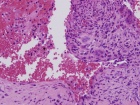

T.K. - 18 year old male with asymptomatic left ankle swelling for several months

Zoom image: Cell stain Cell stain.